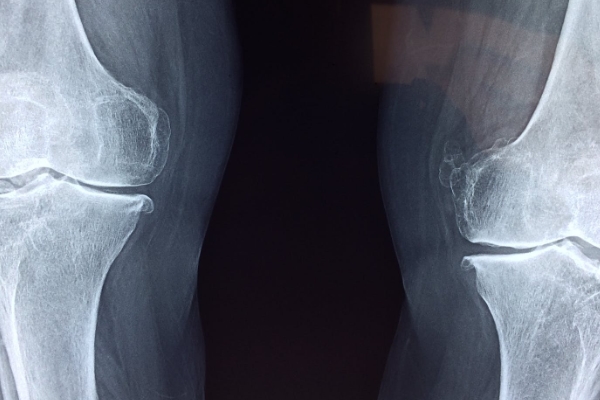

-퇴행성 관절염

퇴행성 관절염은 관절을 보호하고 있는 연골의 점진적인 손상이나 퇴행성 변화로 인해 관절을 이루는 뼈와 인대 등에 손상이 일어나서 염증과 통증이 생기는 질환으로, 관절의 염증성 질환 중 가장 높은 빈도를 보입니다.

통증은 초기에는 해당 관절을 움직일 때 심해지는 양상을 보이다가 병이 진행되면 움직임 여부에 관계없이 지속적으로 나타나기도 하는데요. 관절 운동 범위의 감소, 종창(부종), 관절 주위의 압통이 나타나며 관절 연골의 소실과 변성에 의해 관절면이 불규칙해지면 관절 운동 시 마찰음이 느껴질 수도 있다고 합니다.